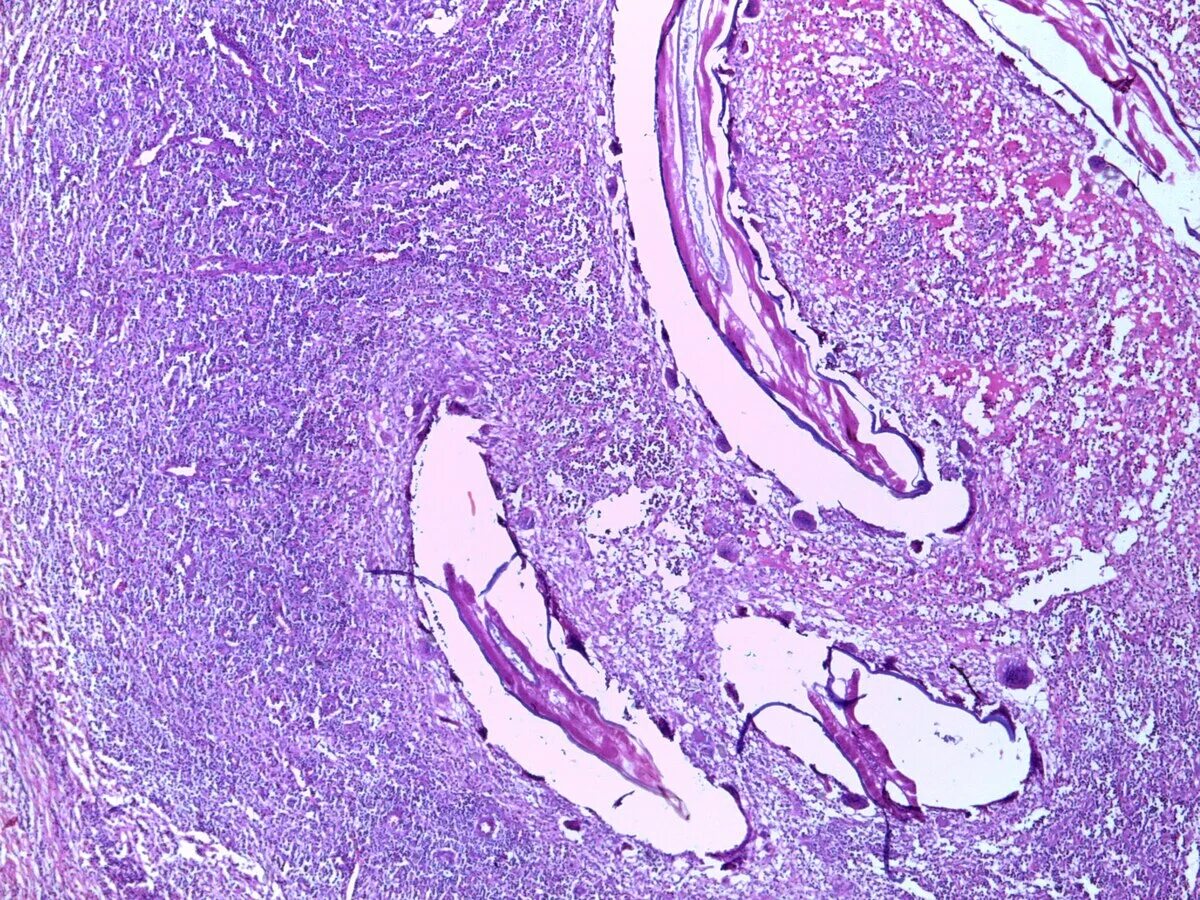

Клетка типа инородных тел